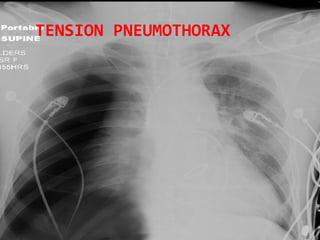

TENSION PNEUMOTHORAX

• #35 Here air has built up under pressure in the pleural space and collapsed the lung severely compromising ventilation. The pressure builds due to a ball valve type leak of air into the pleural space with air going into the space on each inspiration.